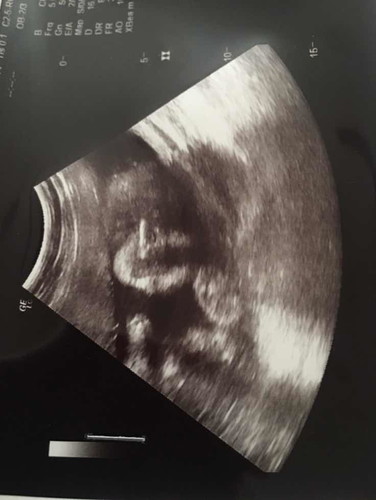

ลุงหมอซาวให้ดูหน้าน้อง แม่ๆว่าเส้นตรงสีขาวๆ ใช่จมูกน้องมั้ยค่ะ☺️ 29/03/63